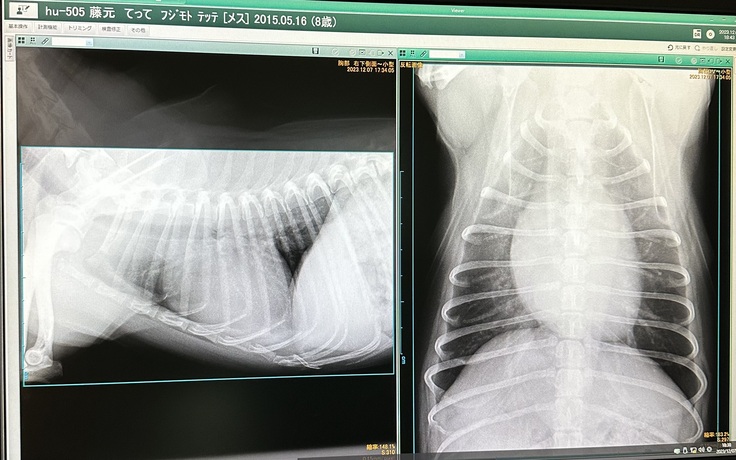

昨年12月7日の心臓検査の診断結果です。レントゲン検査では、心臓が肥大し気管を圧迫しています。

(正常な心臓)

(現在のてっての心臓)

獣医師によれば、下記画像の

左側の赤丸部分は便が正常に閉じていない状態、

右側の色付き部分は便が閉じないことによる血液の逆流を示す。

ということでした。